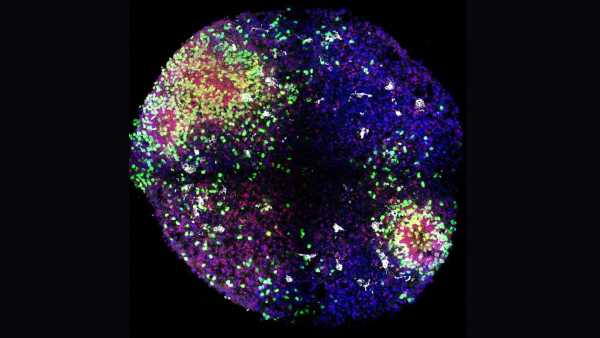

Щоб вивести більш гуманізованих мишей, дослідники спочатку вивели мишей, генетично модифікованих для ослаблення імунної системи. Коли мишам було приблизно 1-2 дні, команда ввела людські стовбурові клітини в серця тварин. Стовбурові клітини, які були вилучені та очищені з пуповинної крові, були здатні перетворитися на будь-який тип імунних клітин.

Потім серця тварин перекачували стовбурові клітини в м’яку губчасту тканину в кістках мишей, відому як кістковий мозок, де зазвичай виробляються імунні клітини. Оскільки миші мали імунодефіцит, людські стовбурові клітини могли легко закріпитися в кістковому мозку.

Через кілька тижнів команда ввела мишам людську версію статевого гормону естрогену. Цей гормон відомий, перш за все, своєю роллю у сприянні жіночому статевому та репродуктивному розвитку, але він також відіграє важливу роль у формуванні незрілих стовбурових клітин у зрілі, спеціалізовані імунні клітини.

Після введення людського естрогену миші почали виробляти безліч людських імунних клітин. Серед них були Т-клітини, які безпосередньо атакують мікроби, та В-клітини, що виробляють антитіла, що знищують бактерії та допомагають позначити патогени для знищення.